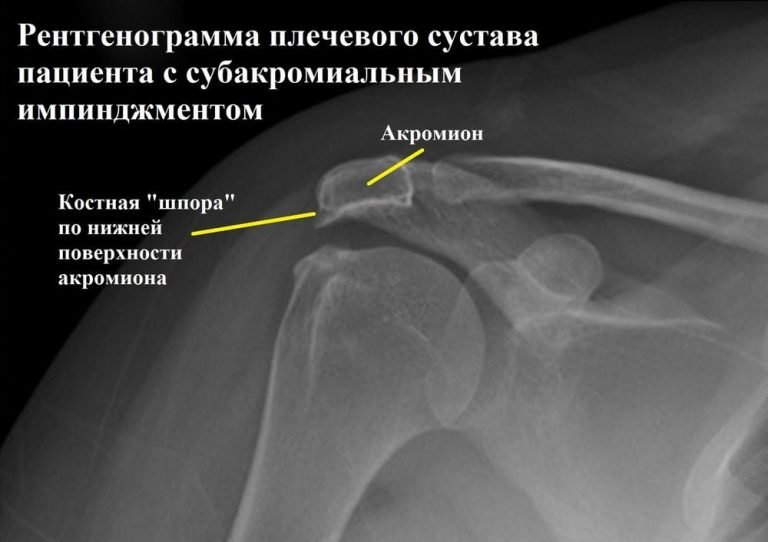

Діагностика: Коли слід звернутися до лікаря